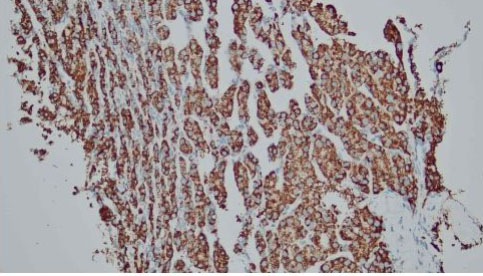

After discussion with the oncologist, a percutaneous biopsy of the right thigh mass was performed in July 2021. The histopathology examination (HPE) from the right thigh mass shows metastatic hepatocellular carcinoma. The malignant cells are positive for hepatocyte stain (Figure 1 and Figure 2). CD34 shows sinusoidal staining pattern (Figure 3 and Figure 4). His AFP at this time was 2.9 ng/mL. He was started on sorafenib but withheld in less than a month due to side effects of vomiting and diarrhea. Soon after discontinuation of the sorafenib he developed obstructive jaundice. Endoscopic retrograde cholangiopancreatography (ERCP) and stenting was done as a palliative intervention. The patient deteriorated and died within a month.

Figure 3: CD34 stain, sinusoidal staining pattern (×10).

Figure 4: Hepatocyte stain, diffuse positive (×10).